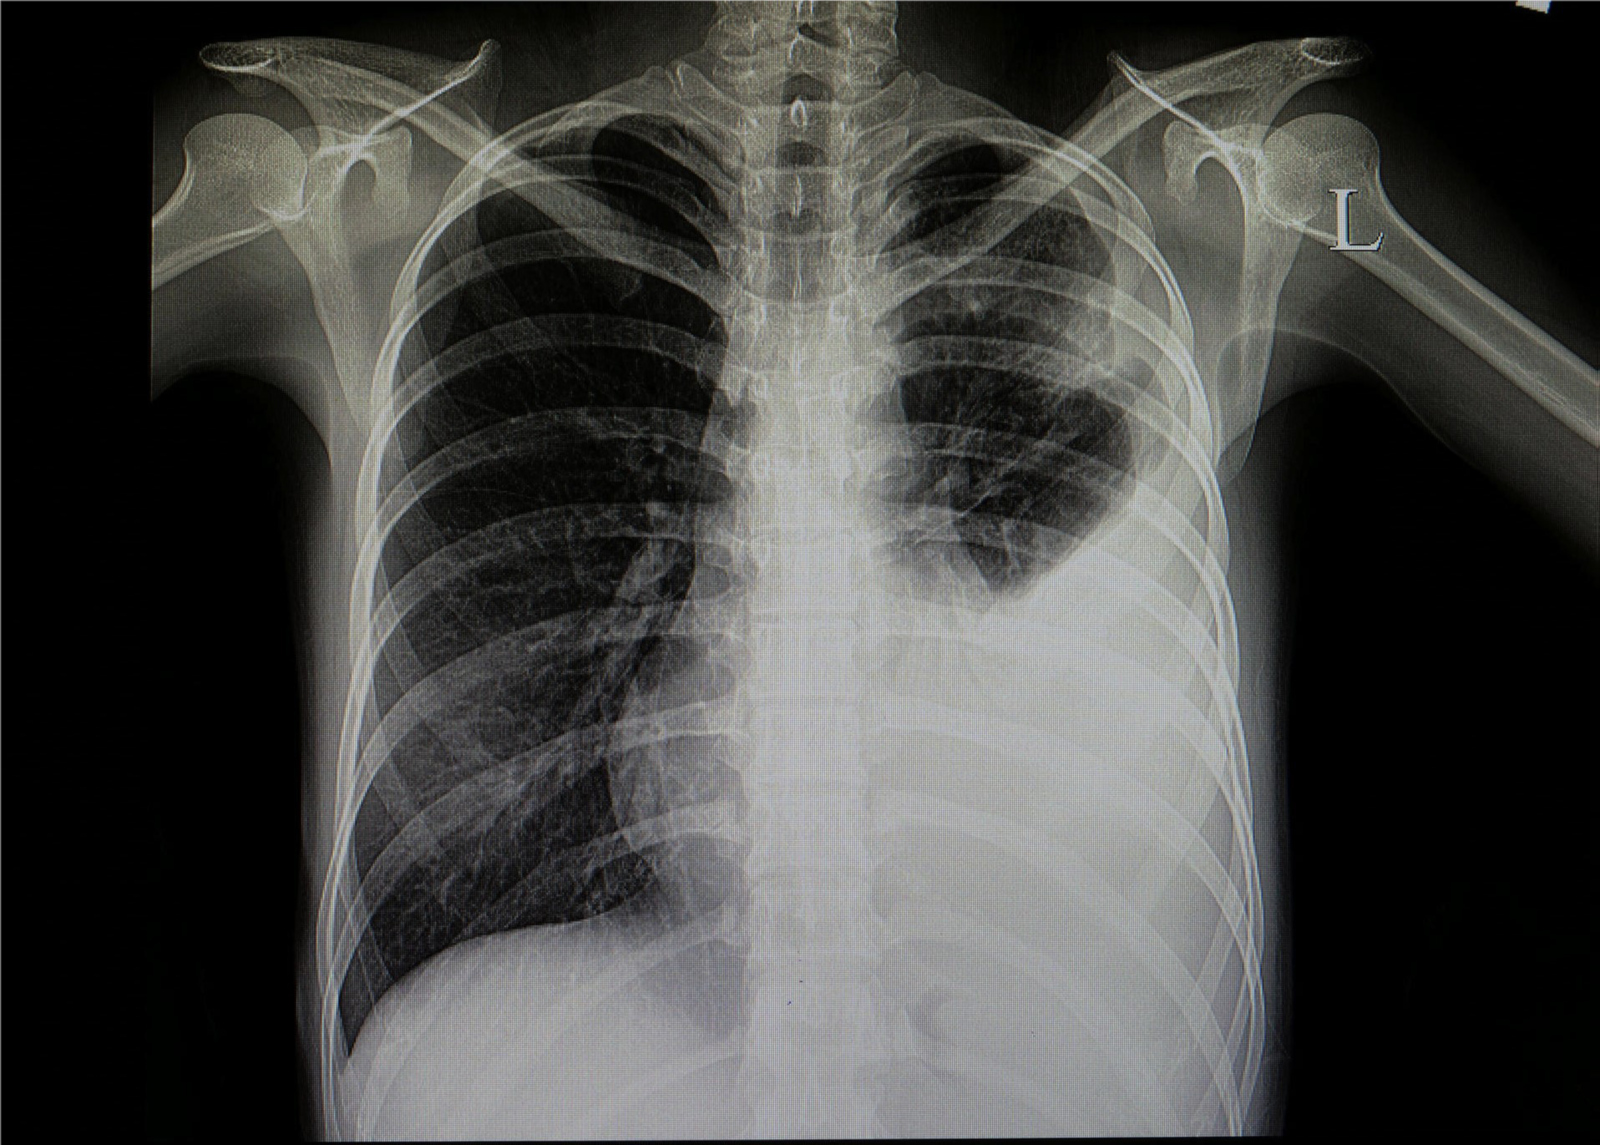

Bei ihrer Arbeit wurde Kopp von ihrem Professor Dr. Alexander Jesser unterstützt. „Bei einer Erkrankung der Lunge ist das betroffene Gewebe meist weniger transparent für die Röntgenstrahlung und kann durch seine Form und Abgrenzung Aufschluss geben, um welche Art der Krankheit es sich handelt. Eine Covid-19-Erkrankung zeigt meist milchglasartige Veränderungen in beiden Lungenflügeln. Ist eine Erkrankung der Lunge durch eine Infektion mit Bakterien erfolgt, ist mehrheitlich nur ein Flügel der Lunge verändert. Eine gleichmäßige Ausbreitung über alle Bereiche der Lunge ist dabei also ein Hinweis auf eine Covid-19 Infektion“, erläutert Jesser.

Damit die Aufnahmen vom Programm ausgewertet werden können, müssen sie in einen Standard-PC eingelesen werden. Danach wird mit einer speziellen mathematischen Operation der Kontrast erhöht. Dadurch können auch qualitativ schlechtere Aufnahmen analysiert werden, die häufig durch ältere Geräte zu Stande kommen. Neben dem Falschfarbenbild erstellt die Software ein sogenanntes „Binärbild“, auf welchem sich bereits die Umrisse der Lunge, sowie Spuren von geschädigtem Gewebe erkennen lassen.

Mithilfe eines weiteren Algorithmus werden die dort vorhandenen Kanten und Grenzen der einzelnen Bereiche ermittelt. Durch weitere Berechnungen werden Flächen- und Symmetriebetrachtungen vollzogen. Dadurch soll letztlich mit großer Wahrscheinlichkeit zwischen bakterieller oder viraler Lungenentzündung unterschieden werden. Dr. Konrad Appelt, Radiologe am Universitätsspital Basel, verweist ebenfalls auf den Nutzen der Software: „Klar ist, dass durch diese Methode ein qualifizierter Arzt nicht ersetzt werden kann und ein einfaches Röntgenbild nicht die diagnostische Qualität eines Computertomographens aufweist, sie kann aber eine sehr sinnvolle, zusätzliche Maßnahme zur Diagnose der Covid-19 Erkrankung sein.“